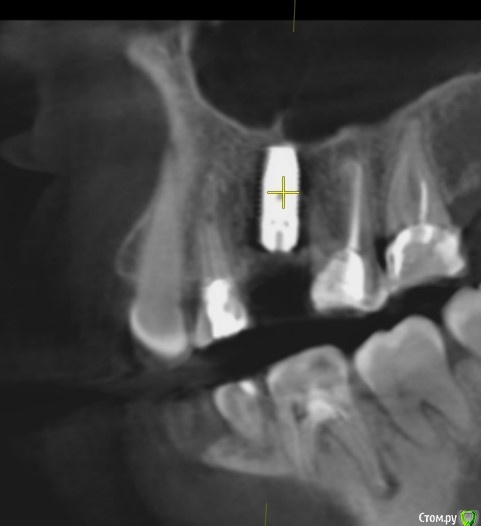

Tatiana72 Опубликовано 27 октября, 2020 Автор Поделиться Опубликовано 27 октября, 2020 Добрый вечер!Выкладываю скрины срезов Ссылка на исследованиеhttps://yadi.sk/d/ViQR0U6R2QjHzg Ссылка на комментарий

Дмитрий М Опубликовано 28 октября, 2020 Поделиться Опубликовано 28 октября, 2020 Добрый вечер!Выкладываю скрины срезовImage4.jpgImage5.jpgImage9.jpg Ссылка на исследованиеhttps://yadi.sk/d/ViQR0U6R2QjHzg не волнуйтесь всё хорошо, по КТ корень зуба не задетесть небольшой очаг разряжения на одном из апексов, обратитесь к стоматологу 1 Ссылка на комментарий